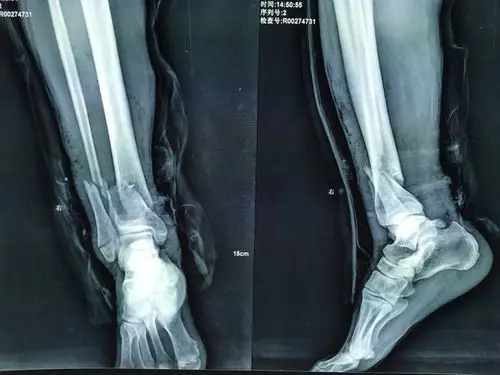

胫腓骨远端骨折

一例严重的胫腓骨远端粉碎骨折

外固定架不开刀治疗胫腓骨远端粉碎性骨折

左胫腓骨远端开放性粉碎性骨折